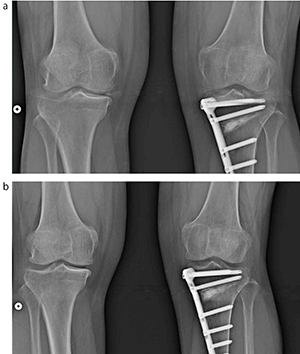

FPDを重ね合わせて撮影し,画像結合を行い長尺画像を作成するので,画像結合部に信号減弱が生じ,画像上にアーチファクトが出現するが,医師からはアライメント計測,その他診断には問題ないとの評価を得ている。ただし,アーチファクトについては,今後もさらなる改良を期待したい(図2)。

図2 画像結合部のアーチファクトの例

結合部との位置関係で出現する。

a:関節間隙にホワイトバンドが出現

b:関節間隙は明瞭である。